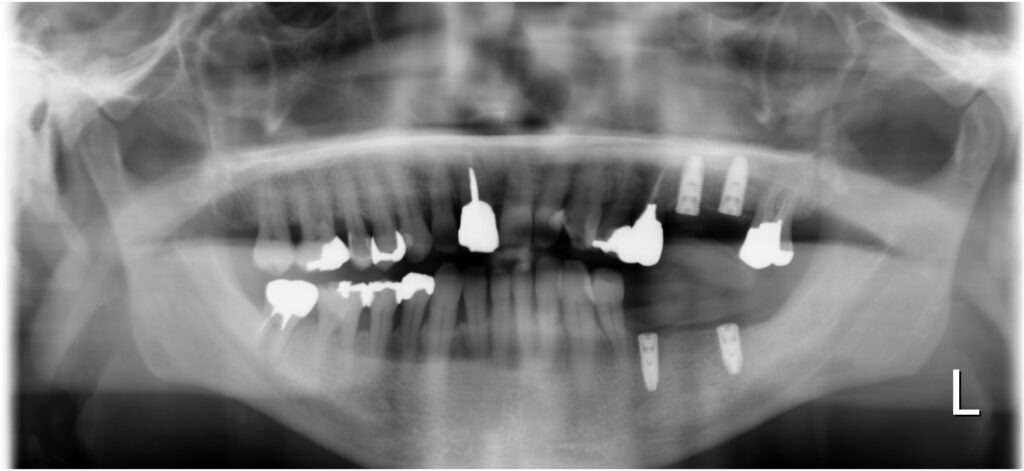

左側上下にインプラント埋入後のパノラマレントゲン写真です。